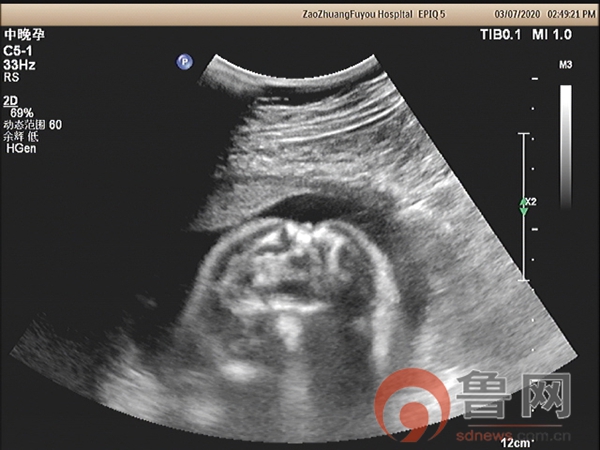

图2:脊髓圆锥低位并局部皮肤缺损

图3骶尾部皮肤连续性中断

该孕妇在18孕周唐筛提示神经管缺陷高风险,又进行了无创DNA检查未见染色体异常,18孕周时外院超声检查未发现明显异常,26孕周+时外院因胎儿“小脑显示异常”转枣庄市妇幼保健院超声科会诊。超声检查显示胎儿头颅呈“柠檬头”状,小脑呈“香蕉状”并后颅窝池消失,枣庄市妇幼保健院具有丰富产前超声筛查经验的超声科专家马上意识到,此例胎儿的头部与小脑形态异常,是“开放性脊柱裂”胎儿头部异常的伴发征象。遵循这个思路,随后仔细扫查胎儿脊椎骨,发现脊髓圆锥位置低于腰4以下,骶尾部皮肤回声中断,胎儿脊柱椎体排列尚规则,脊柱无侧弯,无后凸,做出了“开放性脊柱裂”的最终诊断。该例胎儿脊柱的超声异常征象表现细微,远远不如间接征象表现明显,对于经验不足的年轻超声医师极其容易漏诊,因此对本病例诊断过程提出以下思考: